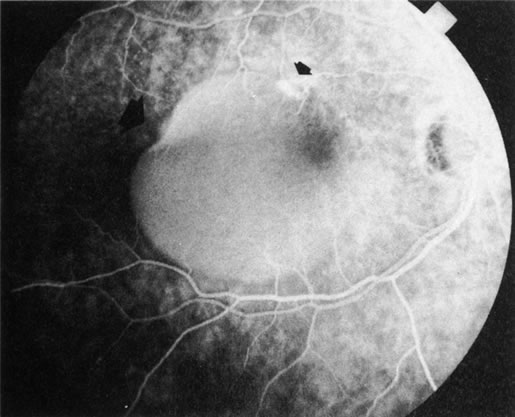

Fig. 20. A. Red-free photograph of a 20-year-old patient with sudden loss of vision to the level of 20/200. There is exudative, neurosensory macular detachment, a few hemorrhages, and lipid exudates. B. Fluorescein angiography reveals the presence of classic choroidal neovascularization (CNV), which appears to be juxtafoveal (<200 μ from fixation). Given the size of the CNV and its proximity to the fovea, it was decided to treat the patient with photodynamic treatment (PDT). C. Red-free photograph of the same eye 2 weeks after PDT; there is increased subretinal exudation D. Fluorescein angiography demonstrates that the CNV is still actively leaking. E. Red-free photograph 4 weeks after PDT demonstrates further increase in the size of the neurosensory macular detachment, subretinal hemorrhages, and lipid exudation. F. Fluorescin angiography reveals that the CNV has extended under the fovea. Given the young age of the patient, an inflammatory component of the neovascular process was suspected. It was decided to give a posterior, subtenon injection of triamcinolone acetonide, 40 mg/1 mL. G. Two weeks after steroid treatment there is partial reabsorption of the subretinal fluid. H. Fluorescein angiography demonstrates contraction of the CNV. I. Four weeks after injection of triamcinolone there is further reduction in the degree of neurosensory detachment; vision had improved to 20/60. J. Fluorescein angiography demonstrates that the CNV is smaller and less active (less leakage).